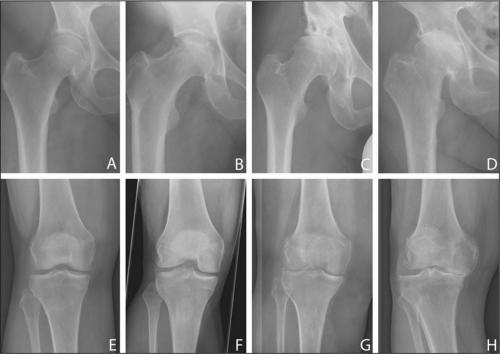

Все медикаментозные средства эффективны лишь на I—II стадиях артроза, но бессильны на III и IV. Если в патологию вовлечены не только суставы, но и кости, никакой препарат не поможет. В этом случае избавиться от хронических болей в суставах, трудностей при ходьбе, ограниченной подвижности суставов и других неприятных симптомов можно только с помощью операции.

Следует также отметить, что результат лечения сильно зависит от стадии развития заболевания.

Чем раньше обнаружен остеохондроз и назначено лечение, тем выше эффект.